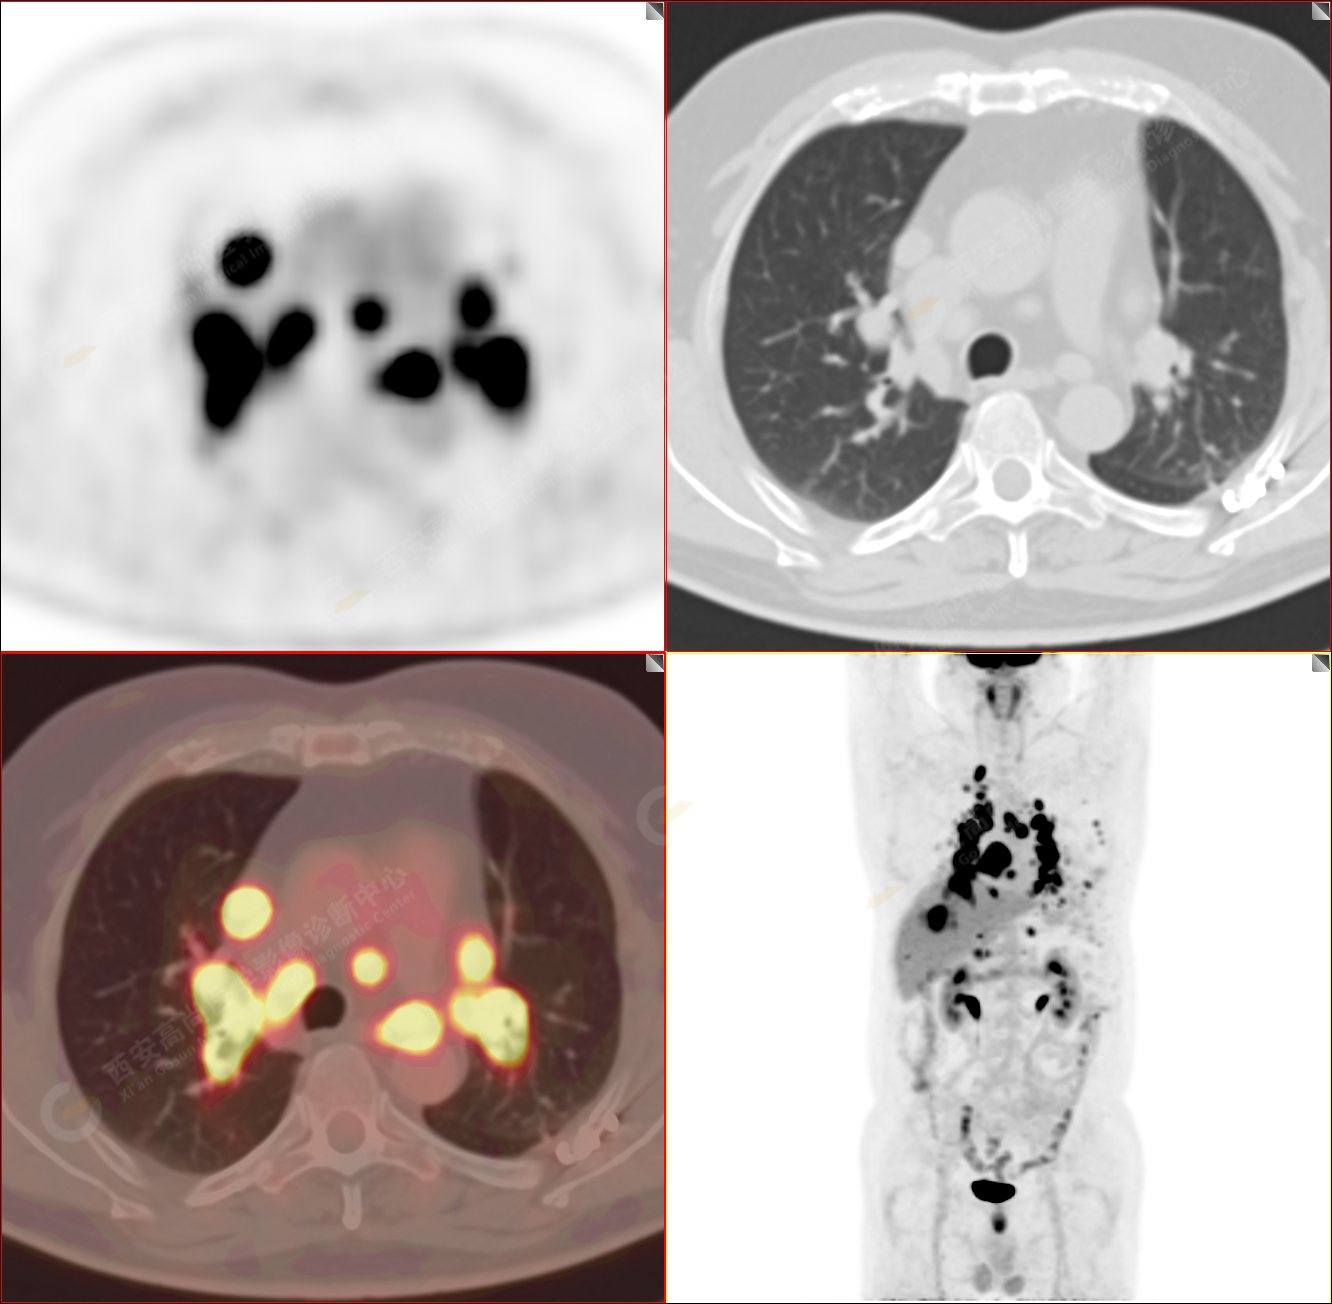

男性,53歲,頭暈半月入院,CT發(fā)現(xiàn)肺內(nèi)腫塊,雙肺多發(fā)大小不等實性及粟粒樣結(jié)節(jié),雙肺門及縱隔多發(fā)腫大淋巴結(jié)。病程中無發(fā)熱、胸悶氣及胸部不適。既往:左側(cè)肋骨外傷史。

PET-MR圖像